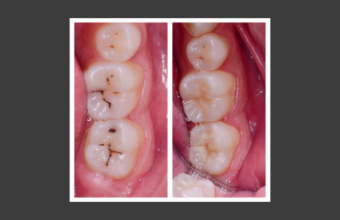

Фиссурный кариес – лечение у взрослых и детей

Фиссурный кариес относится к распространенным стоматологическим проблемам, особенно у детей и подростков, хотя нередко диагностируется и у взрослых. Начальная стадия нередко протекает без симптомов, а при углубленном разрушении дентина помимо пломбирования потребуется ...